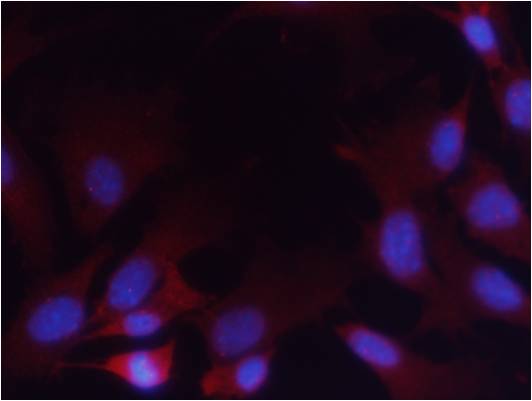

The PTEN (Phospho-Ser380/Thr382/Thr383) antibody specifically detects these phosphorylation sites, enabling researchers to investigate PTEN inactivation mechanisms in diseases like cancer, where dysregulated PTEN contributes to hyperactivated PI3K/AKT signaling. It is widely used in techniques including Western blotting, immunohistochemistry, and immunofluorescence to assess phosphorylation status in cell lines, tissues, or preclinical models. Studies utilizing this antibody have clarified how PTEN phosphorylation impacts cellular localization, protein-protein interactions, and tumor suppressor function, offering insights into therapeutic strategies targeting PTEN-related pathways. Proper controls, such as phosphorylation-deficient mutants, are essential to confirm antibody specificity.